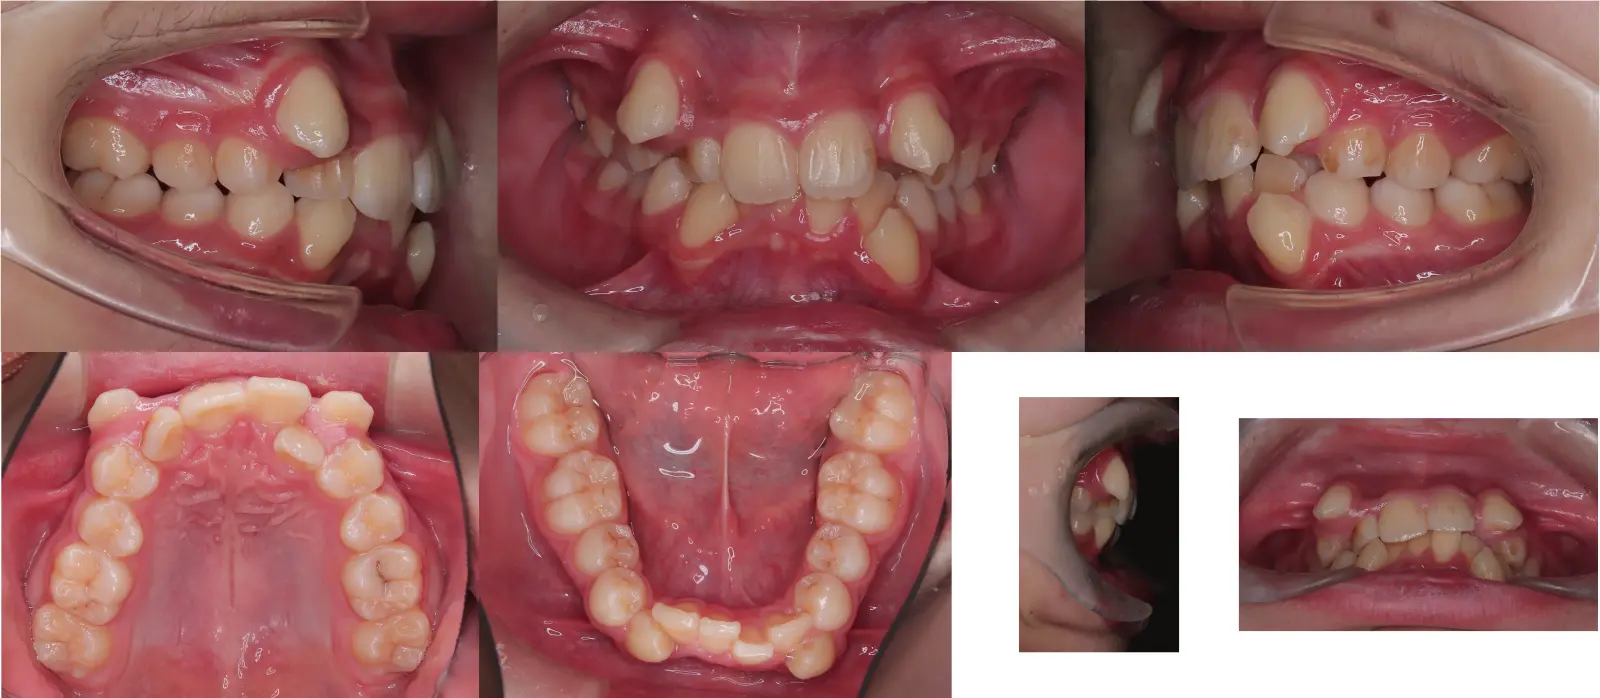

アングルⅠ級、過蓋咬合を伴う叢生

- 主訴

乱食い歯

- 年齢

20代

- 治療期間

1年7ヶ月

- 治療回数

18回

- 治療に用いた主な装置

上下顎共にカスタムメイド型リンガルブラケット矯正装置 (WIN)

- 治療費

1,350,000円(税別)トータル料金

- 抜歯部位

非抜歯治療による治療